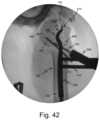

FIGS.38-42 illustrate a procedure for implanting an intramedullary nail utilizing a guide assembly in accordance with an embodiment of the disclosure.

Referring toFIGS.38-42, another method of implanting an intramedullary nail utilizing an external guide in accordance with an embodiment of the disclosure will be described. The following procedure, although provided in the context of proximal humerus fixation, can be used for periarticular fractures in other anatomical locations.

Referring toFIGS.41 and42, the aimingguide720 is positioned on theposts710. The aimingguide720 includes abody722 defining a pair holes724 which align with and receive the free ends711 of thedistal posts710. In this way, theposts710 align the aimingguide720 with theimplant610. Set screws or the like may be positioned inholes726 in the side of thebody722 and engage grooves712 (seeFIG.40) near thefree end711 of eachpost710 to lock the aimingguide720 in place. A plurality of guide holes728 extend through thebody722, with eachguide hole728 aligned with arespective screw hole630,646 of theimplant610.Screws160 are then inserted throughguide sleeve582 positioned in the guide holes728 as shown inFIG.42. Once thescrews160 are inserted, theposts710 may be removed and screws160 may be optionally inserted in theholes626. While thealignment guide700 and aimingguide720 are illustrated as separate components, it is understood, the functionality can be provided in a single guide with a removable arm, similar to the guide assembly above.